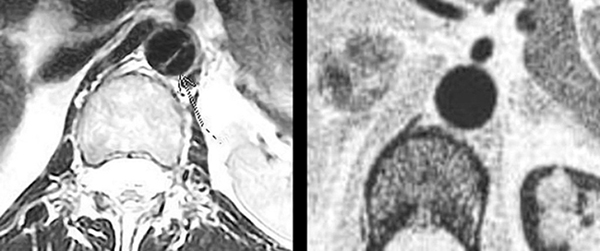

Трис Гриффин

Трис Гриффин обратилась к врачу в начале 2013 года из-за боли в пояснице, которая, как она опасалась, могла быть рецидивом её борьбы с раком. Томография показала “расслоение аорты” в её сердце, что побудило врачей провести дальнейшие тесты и наметить неотложную операцию на следующий день. На фото ясно видна линия, которая проходит через сердце – очевидно, что это трещина, которая означала бы быструю и почти неминуемую смерть в случае разрыва.

На следующий день, после того, как верующие помолились за неё, врачи провели ещё одну компьютерную томографию, чтобы точно определить местоположение трещины перед операцией. На этот раз снимки показали абсолютно здоровое сердце. Весьма озадаченный, хирург сказал миссис Гриффин: “Я не знаю, что вам сказать. У вас было расслоение аорты, но теперь от этого не осталось и следа”. Он показал ей снимки сделанные до и после молитвы. “Вы можете идти. И между прочим, у вас также нет никакого рака. Вы абсолютно здоровы”.

Стрелка, нанесённая врачом, указывает на аорту, которая представляет собой темную, круглую областью в центре изображения. Диагональная линия – это аневризм или расслоение аорты, которая нуждается в срочной операции и может оказаться фатальной в случае разрыва. На следующий день был осуществлено второе сканирование сердца. Расслоение полностью исчезло и никогда больше не возникало.